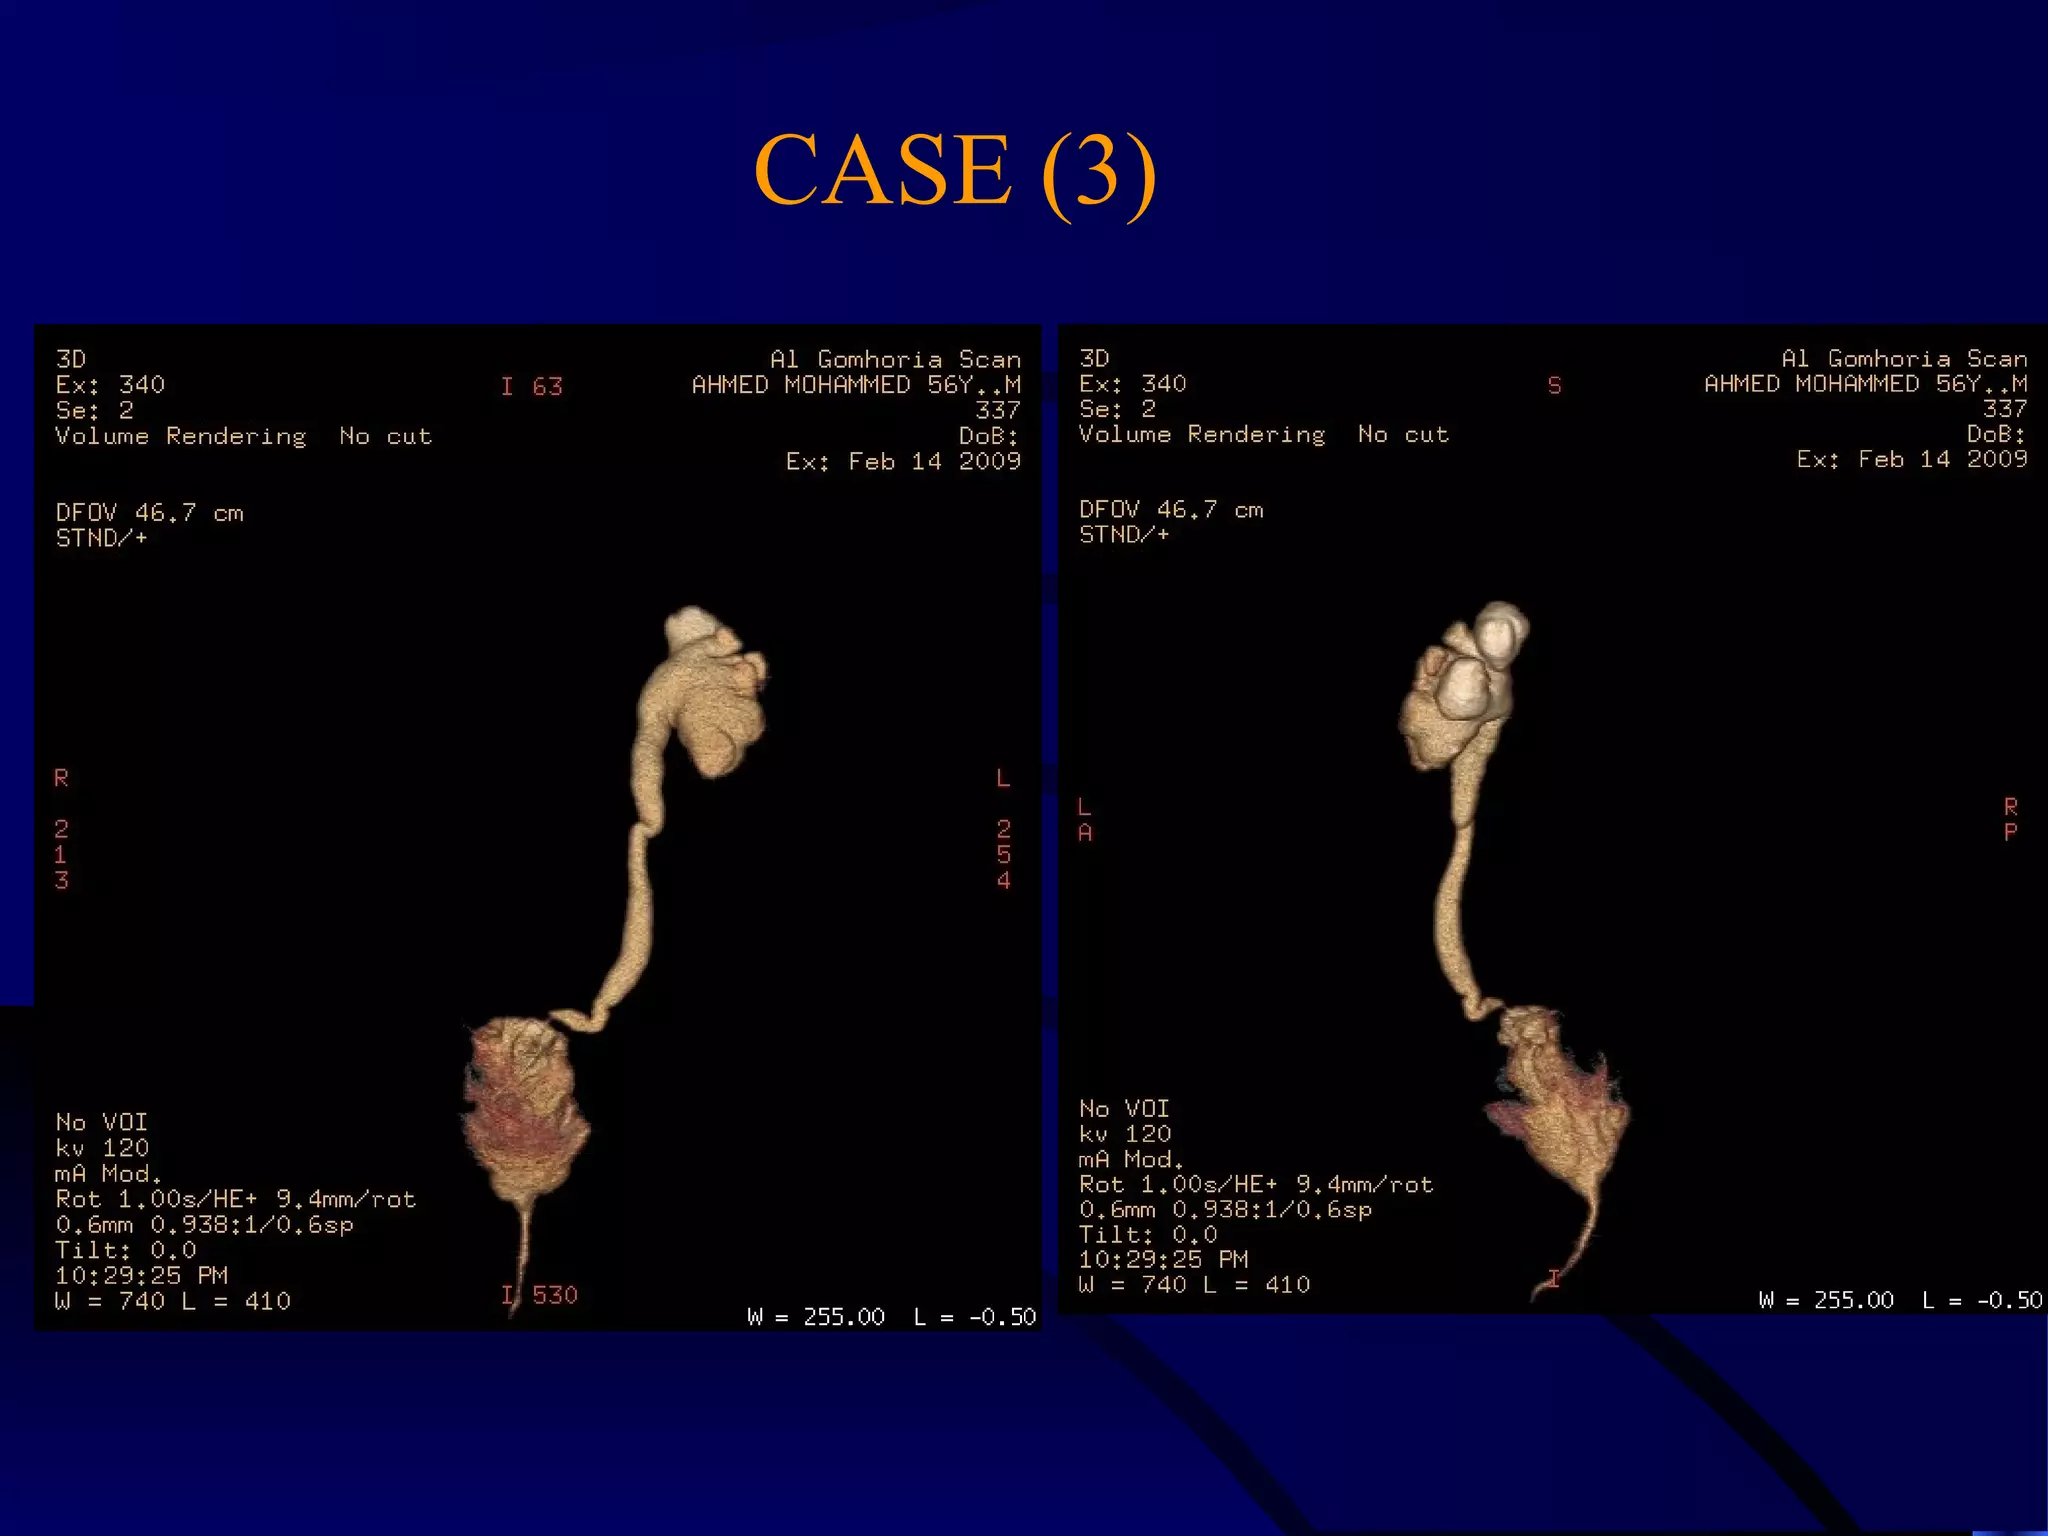

CASE (3)